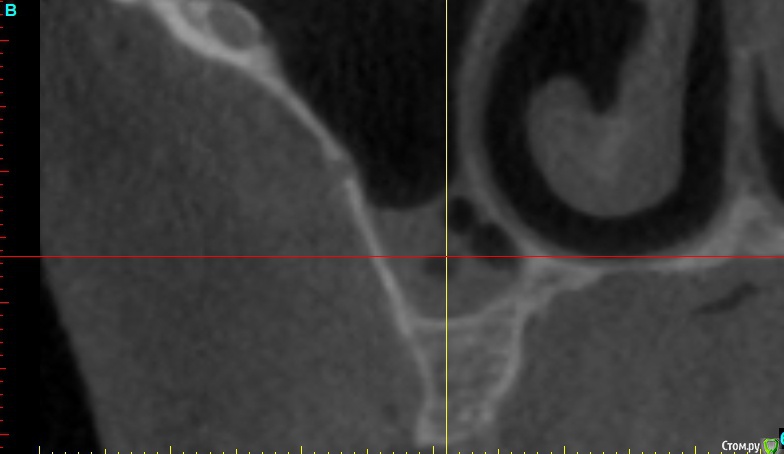

x4ex Опубликовано 7 ноября, 2018 Поделиться Опубликовано 7 ноября, 2018 Добрый день, коллеги! Планируется синус-лифт справа, по словам пациент ЛОР сказал, что противопоказаний не видит. Якобы есть полипы, которые он может убрать эндоскопически, но смысла в этом не видит, потому как со временем они вырастут снова. Но мне картина на КТ похожа не на полипы, а на жидкость с пузырьками воздуха. Кто что думает, стали бы синусить? Ссылка на комментарий

x4ex Опубликовано 11 ноября, 2018 Автор Поделиться Опубликовано 11 ноября, 2018 Судя по срезу, там гайморит вторичен. Пусть ЛОР посмотрит этмоидальные..ЛОР в заключении написал "полипозный этмоидит" Ссылка на комментарий

___49___ Опубликовано 12 ноября, 2018 Поделиться Опубликовано 12 ноября, 2018 (изменено) У пациента , фронтит, гайморит двусторонний и этмоидит в стадии ремиссии (сопли) скорее всего , проблемы чисто ЛОРа . Лучше решать вопрос без задействования синуса ИМХО. Изменено 12 ноября, 2018 пользователем ___49___ Ссылка на комментарий